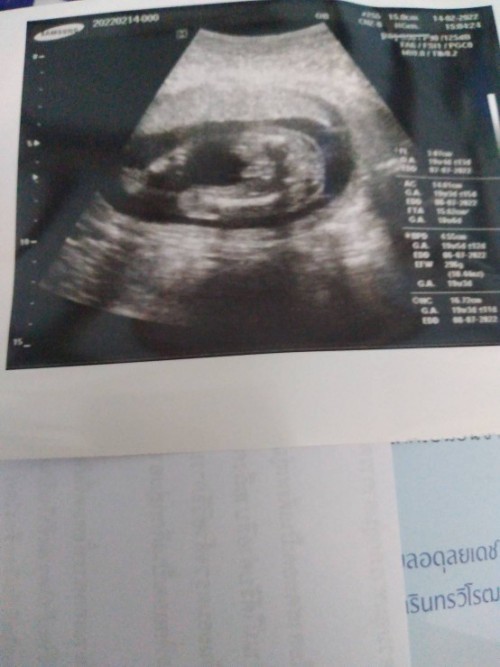

ตอนนี้ 19w 4 ลูกสาวค่ะ ❤️

Post reply image